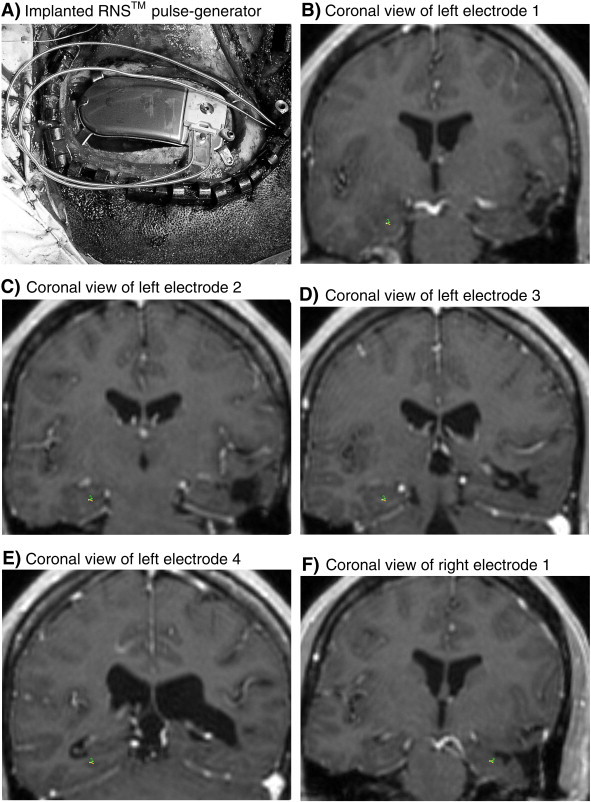

Fig. 1.

Image coregistration after device implantation. (A) The pulse generator is affixed within a ferrule in the skull and attached to the leads in the brain (not visible) by an insulated electrical conductor that is tunneled under the scalp. (B–I) Implanted electrodes in coronal view of coregistration where each aspect is orthogonal to the long axis of the hippocampus.

A track per DBS lead (NeuroPace, Mountain View, CA) targeted each anterior hippocampus using the microTargeting WayPoint Planner 2.0 software (FHC, Inc., Bowdoin, ME). Occipital lead entry points were chosen to avoid the ventricles, prominent veins, and arteries as visualized by the preoperative coregistered volumetric MRI and CT scans. On each side, a recording (Figs. 2A–E) was performed before implanting one four-electrode DBS lead, which was then connected to the pulse generator embedded in the right side of the skull (Fig. 1A).

The RNS™ device automatically stored four bipolar ECoG signals for each seizure: signals L1, L2, R1, and R2 respectively represented left electrodes 1–2, left electrodes 3–4, right electrodes 1–2, and right electrodes 3–4 (Figs. 1B–I). For each seizure, the RNS™ stored the four signals with corresponding date and timestamps (60 s before and 30 s after detection).